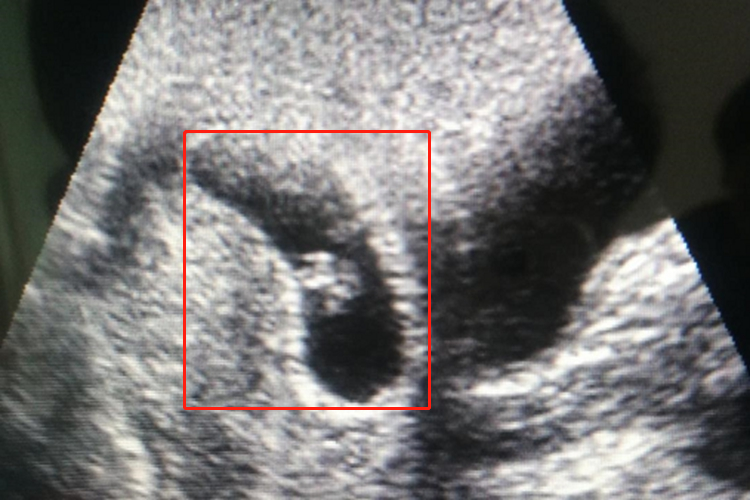

刚怀孕胎儿即孕4-5周的胎儿,一般未具有人形,主要通过超声检查见到圆形或椭圆形的妊娠囊,即为早期胎儿。在声像图上妊娠囊在子宫内显示为一圆形或近圆形的厚壁环状中等回声,中心为圆形或类圆形的无回声区。妊娠囊饱满,无皱缩变形,囊壁应完整、光滑,厚度基本均匀,其回声强,早期超声于无回声区内不能发现任何结构。